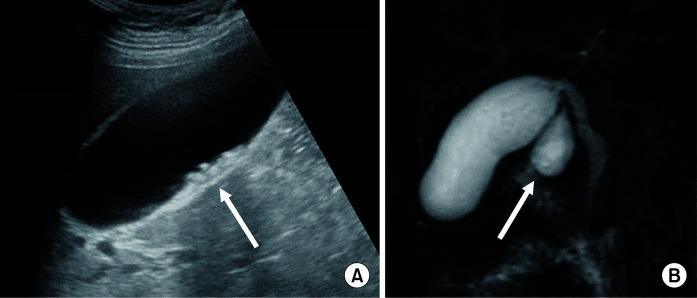

同时腹腔镜下切除托达尼II型胆总管囊肿和微结石性胆囊炎。

Simultaneous laparoscopic removal of a Todani type II choledochal cyst and a microlithiasic cholecystitis.

Diverticula of the choledochus, better known as Todani type II cysts, are very rare and represent a predominantly pediatric pathology. Their identification by radiological methods, even if occasional, requires clinical doctors to request a surgical consultation, even for asymptomatic subjects, to proceed with their removal, given the risk of associated neoplasms. The laparoscopic approach for surgical treatment of these cysts has been recently introduced with excellent results. Due to the poor clinical records, currently there are neither shared protocols about their management nor long-term follow-up of operated patients. We report a case of an adult female suffering for years from biliary colic due to the presence of a duodenal diverticulum associated with microlithiasis' cholecystitis, who was laparoscopically treated, with excellent results in terms of symptomatic regression, reduced hospitalization, and no surgery-related complications.

胆总管憩室,更常见的是托达尼II型囊肿,非常罕见,主要是儿科疾病。通过放射学方法识别它们,即使是偶尔发现,鉴于存在相关肿瘤的风险,临床医生也需要进行手术会诊,即使是无症状患者,以便进行切除。腹腔镜手术治疗这些囊肿的方法最近已被引入,效果良好。由于临床记录不佳,目前对于它们的处理既没有共享的方案,也没有对手术患者的长期随访。我们报告一例成年女性病例,因存在与微结石性胆囊炎相关的十二指肠憩室,多年来饱受胆绞痛之苦,接受了腹腔镜治疗,在症状缓解、住院时间缩短且无手术相关并发症方面取得了良好效果。